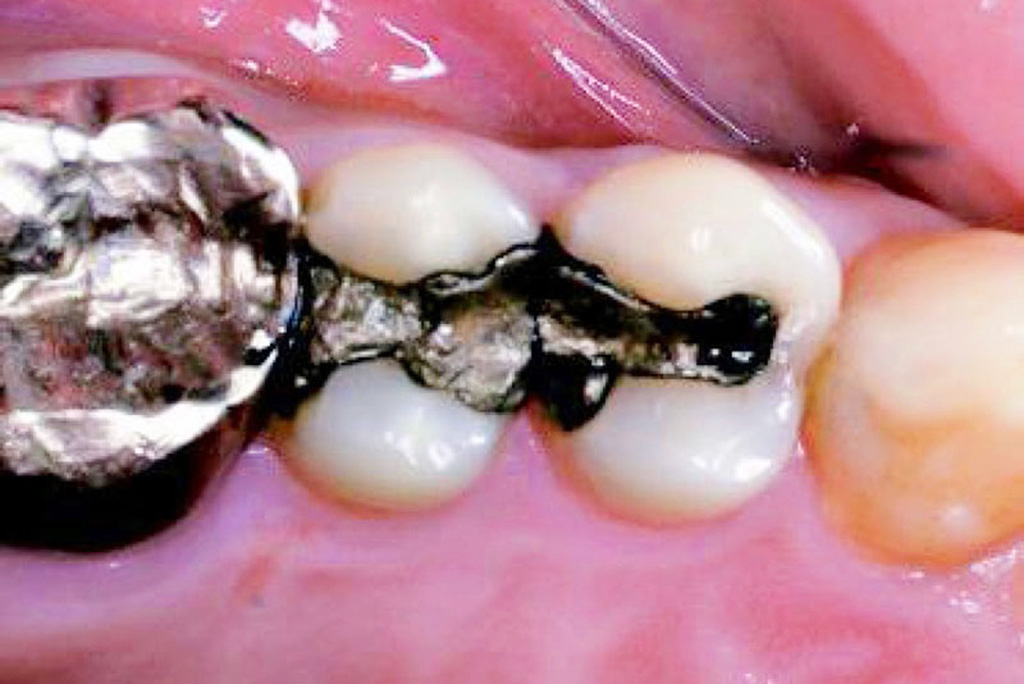

以前は、根尖病変などから

排膿している歯肉の開口部を

【フィステル(瘻孔)】と呼んでいました。

しかし現在は、

サイナストラクト(sinus tract)

という名称が使われることが増えています。

一方、歯科で見られる多くの排膿路は、

そのため、より正確な用語として

【サイナストラクト(排膿路)】が

用いられるようになりました。